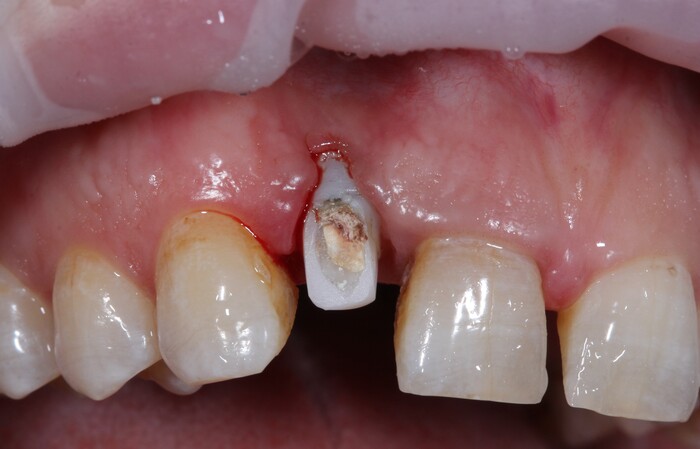

После снятия коронки:

Выкрутили абатмент:

Установлена заглушка, которая закрывает шахту имплантата.

Теперь необходимо выждать около 2-х месяцев для того, чтобы десна восстановилась (Пациентка это время ходила со специальной капой, которая имитирует наличие зуба).